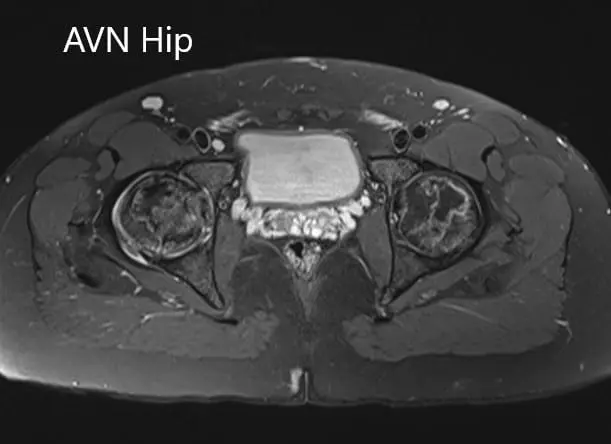

Axial sections of the T2WI and T1WI of MRI.

Hypointense areas were present on both T1WI and T2WI on both the head of the femur suggestive of sclerosis. Surrounding bone marrow edema was present and the bilateral necrotic area was approximately 70%.